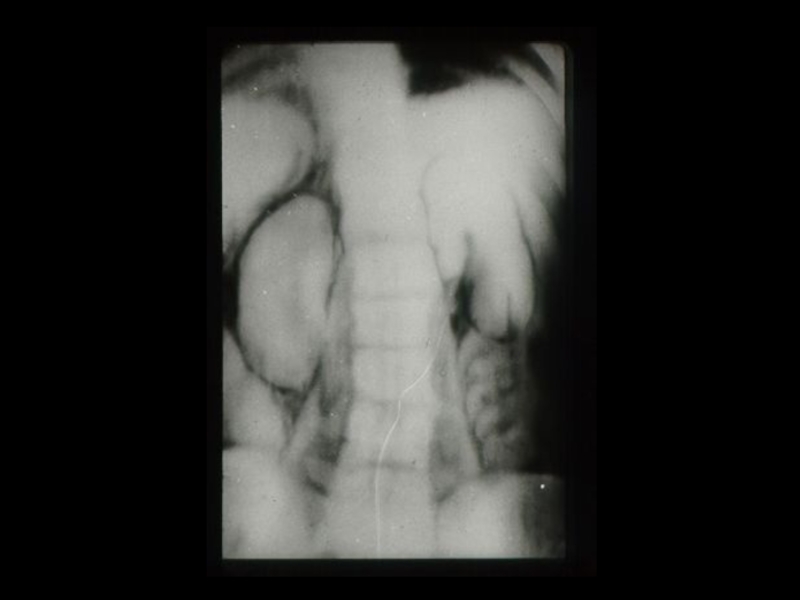

Слайд 18Методы традиционной рентгенодиагностики:

1. Общие методы

(рентгеноскопия, рентгенография)

2. Частные

методы

(флюорография, томография,

электрорентгенография, маммография и

другие)

3. Специальные методы

(урография, бронхография, ангиография,

лимфография, пневмоартрография и другие)

Методы традиционной рентгенодиагностики:1. Общие методы   (рентгеноскопия, рентгенография)2. Частные методы   (флюорография, томография,